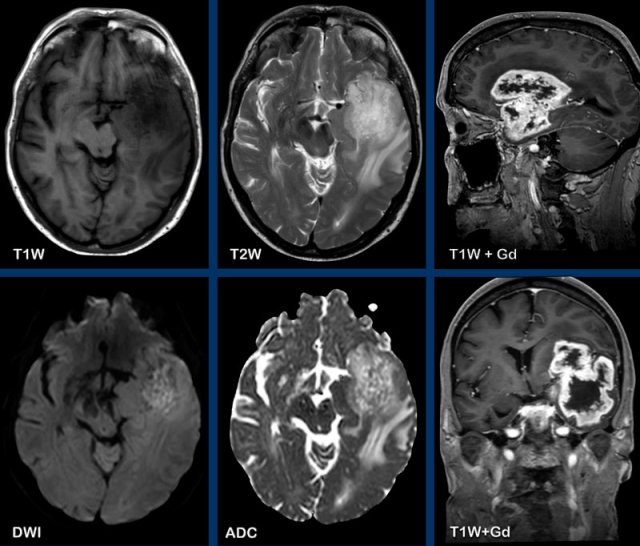

These images are of a 47-year old male, who presented with headache, vomiting and a right-sided hemiparesis.

Images

A ring enhancing lesion is present in the left basal ganglia.

Note the enhancing structures within the inner border of the

enhancement.

There is no diffusion restriction, which makes the diagnosis of an abscess unlikely.

This is a pathologically proven GBM.

These images are of a 55-year old patient, who presented with headache and aphasia.

First look at the images and then continue reading.

- What are the findings?

- What is the most likely diagnosis?

There is a left

frontotemporal lesion, which is bright on T2W, with thick and irregular ring enhancement.

The lesion follows - and extents into the white matter like

the uncinate fasciculus and the u-fibers.

The centre of the lesion shows no diffusion restriction and no enhancement and is most likely necrosis.

The most likely diagnosis is a GMB.

Glial

tumors originate from glial cells in the central nervous system and are

infiltrative tumors.

GBM’s are the most malignant primary brain

tumors.

They diffusely infiltrate along the white matter tracts, as e.g. the

corpus callosum.